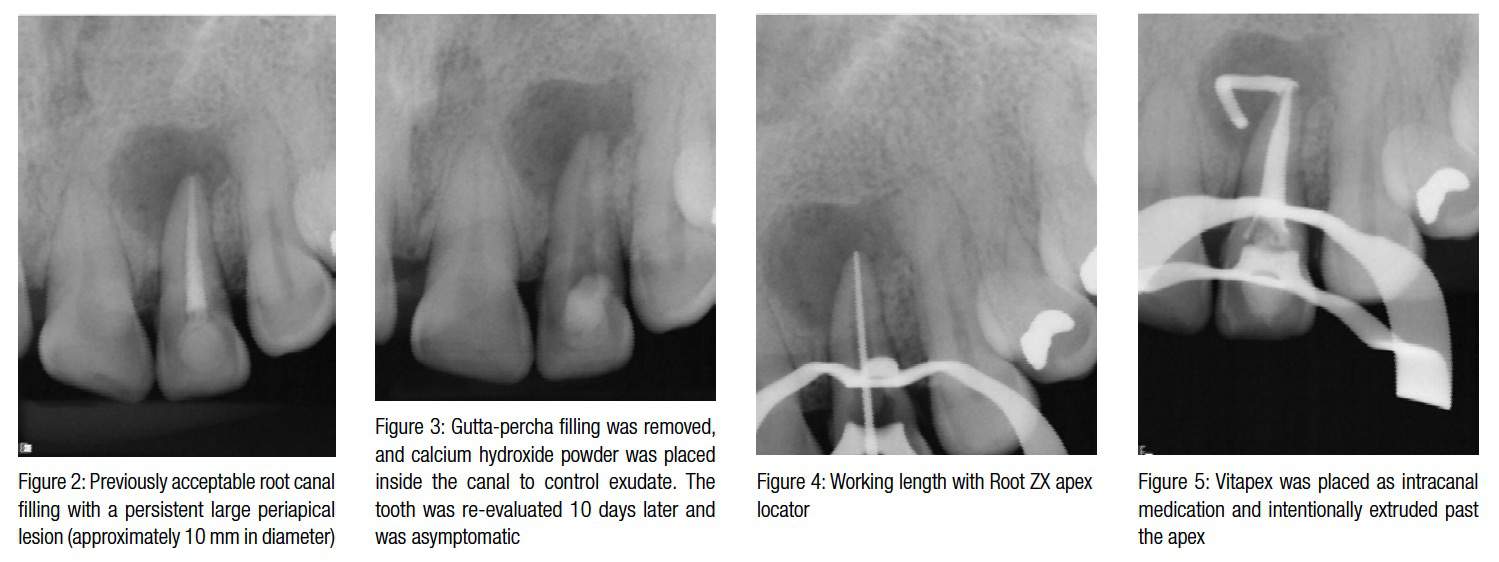

Nonsurgical endodontic retreatment of extensive periapical lesions Endodontic Lesions Examples Mandibular molars can also have accessory canals in lateral orientation or in the furcation area. In this chapter, a systematic diagnostic process involving detailed history taking and thorough clinical and radiographic. A, primary pulpal infection can lead to chronic periradicular periodontitis by which a periapical radiolucency (parl) can develop and migrate cervically. Dentists are likely to encounter lesions that have. Endodontic Lesions Examples.